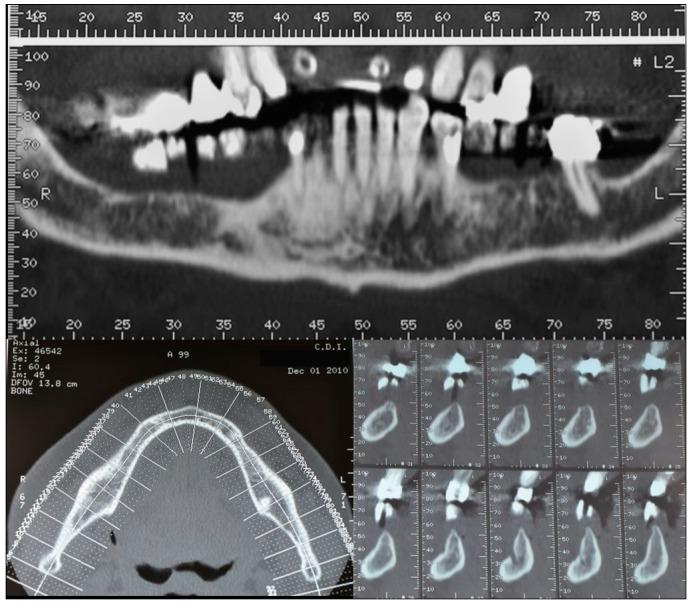

One of the most often used bone augmentation techniques is the guided bone regeneration procedure. The authors report the case of a 75-year-old man with an atrophic right posterior mandible who underwent bone augmentation through guided bone regeneration with a preshaped titanium mesh adapted on a stereolithographic model of the patient's jaw. The graft volume was simulated with a light-curing resin. The actual site was grafted with a mixture of autogenous and equine-derived bone. Five months later, the mesh was retrieved, three cylindrical implants were positioned, and a bone biopsy was collected for histomorphometric analysis. A provisional prosthesis was delivered three and a half months later. Definitive rehabilitation was accomplished after one additional month. The graft allowed for effective bone formation (newly formed bone, residual biomaterial, and medullar spaces were, respectively, 39%, 10%, and 51% of the core volume). The patient has functioned successfully throughout six and a half years of follow-up. Using the preshaped titanium mesh in association with the enzyme-treated equine bone substitute provided effective bone regeneration.

最常用的骨增量技术之一是引导骨再生术。作者报告了一例75岁男性患者,其右侧下颌骨萎缩,通过引导骨再生术进行骨增量,使用了根据患者颌骨的立体光刻模型定制的预成型钛网。用光固化树脂模拟移植骨体积。实际部位植入了自体骨和马源骨的混合物。五个月后,取出钛网,植入3枚圆柱形种植体,并采集骨活检样本进行组织形态计量学分析。三个半月后安装临时义齿。再过一个月完成最终修复。移植骨实现了有效的骨形成(新形成的骨、残余生物材料和骨髓腔分别占核心体积的39%、10%和51%)。在六年半的随访期间,患者功能良好。使用预成型钛网联合酶处理的马骨替代物可实现有效的骨再生。